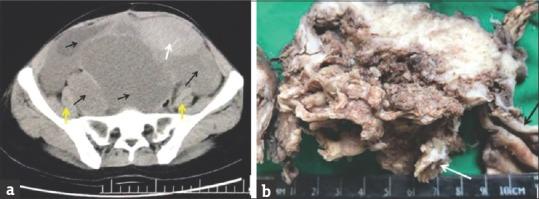

Pure squamous cell carcinoma (SCC) of the ovary is rare. SCC can arise in a mature teratoma (MT), ovarian endometriosis or in a Brenner tumor. SCC is the most common malignant transformation arising in MT and comprises 80% of all cases. Such neoplastic transformations are extremely difficult either to predict or detect early. The mechanism of malignant transformation has not been completely understood. Due to the rarity and the aggressive course, diagnosis and treatment constitute a big challenge. We report a case of SCC arising in MT presenting with a huge abdominopelvic mass and abundant peritoneal collections clinically masquerading as abdominal tuberculosis. A review of literature with special emphasis on prognosis and treatment modalities is also presented.

卵巢纯鳞状细胞癌(SCC)较为罕见。SCC可发生于成熟畸胎瘤(MT)、卵巢子宫内膜异位症或勃勒纳瘤。SCC是MT中最常见的恶性转化类型,占所有病例的80%。这种肿瘤转化极难早期预测或检测。恶性转化的机制尚未完全明了。由于其罕见性及侵袭性病程,诊断和治疗构成了巨大挑战。我们报告1例发生于MT的SCC病例,临床表现为巨大的腹盆腔肿块及大量腹腔积液,临床上易误诊为腹部结核。本文还对文献进行了综述,特别强调了预后及治疗方式。